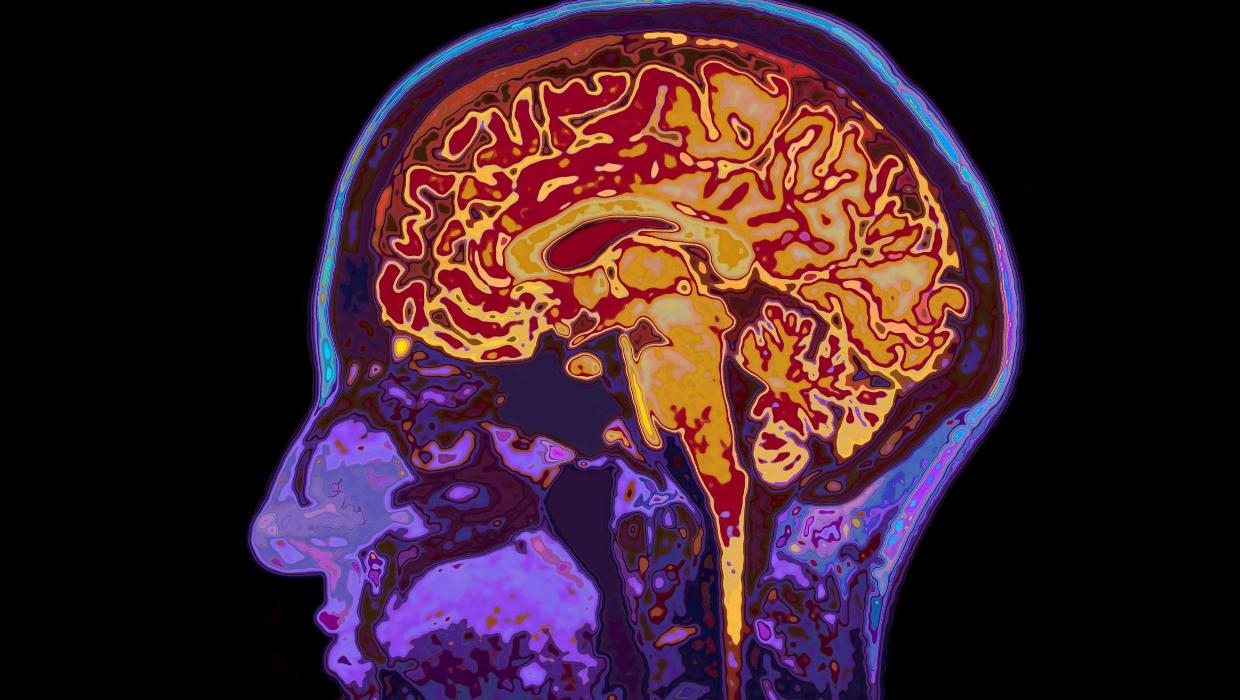

Research conducted by the University of Cambridge has revealed that human brain development extends into the early thirties, with significant changes occurring during this period. The study identifies five major epochs of brain growth, highlighting four critical turning points in an individual’s life.

The findings suggest that the brain continues to evolve until approximately age 32, challenging the long-held belief that brain maturity is reached in the early twenties. This extended developmental phase may have implications for understanding behavior and decision-making in young adults.

According to the study, which is grounded in extensive neurodevelopmental research, the five epochs mark distinct phases in cognitive and emotional growth. The first epoch begins in childhood, characterized by rapid development and the establishment of foundational skills. Subsequent epochs reflect significant milestones, including adolescence and early adulthood, culminating in a more stable phase that begins around age 32.

The study’s authors emphasize that these findings are critical in recognizing how brain maturity influences social interactions, educational trajectories, and overall life choices. The fourth turning point occurs at around age 66, when the brain starts to show signs of aging, such as decreased cognitive flexibility and slower processing speeds.